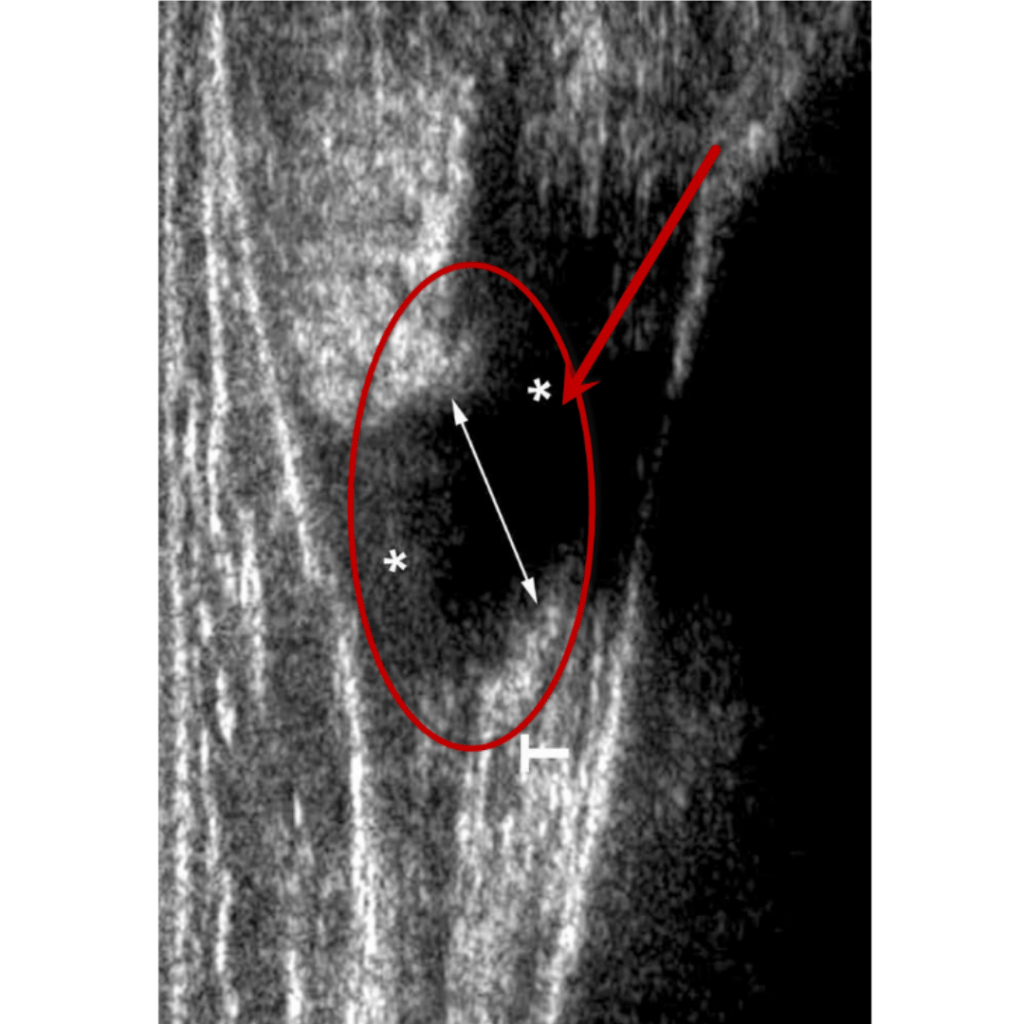

El diagnóstico de esta afectación dependerá mucho de su localización, en caso de sospecha de compromiso en un músculo superficial se puede hacer uso de ecografía (ultrasonido), en tejidos más profundos es más eficiente una resonancia magnética.

Ultrasonido Ruptura total Grado III